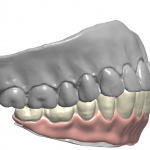

Digital extractions performed in preparation for overdentures

Overdenture Design and Fabrication